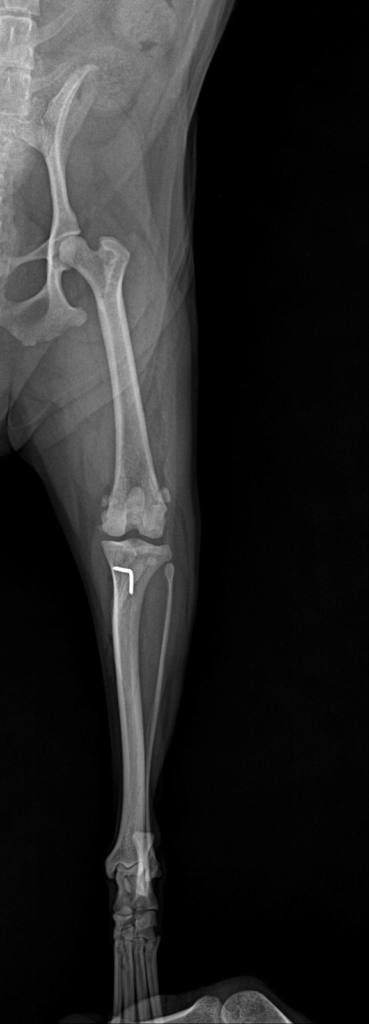

수술 후 엑스레이에서는 슬개골이 정상적으로 대퇴골 고랑 안에 안정적으로 위치한 것이 확인되었습니다.

수술 후 x-ray 사진 / 출처: 미래동물의료센터

수술 후 촬영한 엑스레이에서 수술 전에는 내측으로 벗어나 있던 슬개골이 대퇴골 고랑 안에 정상적으로, 안정적으로 위치해 있는 것이 확인되었습니다.

이는 수술의 구조적 교정이 잘 이루어졌다는 중요한 지표입니다. 환자는 입원 치료를 마친 뒤 무사히 퇴원했고, 현재는 통원 치료와 회복 과정을 안정적으로 이어가고 있습니다.